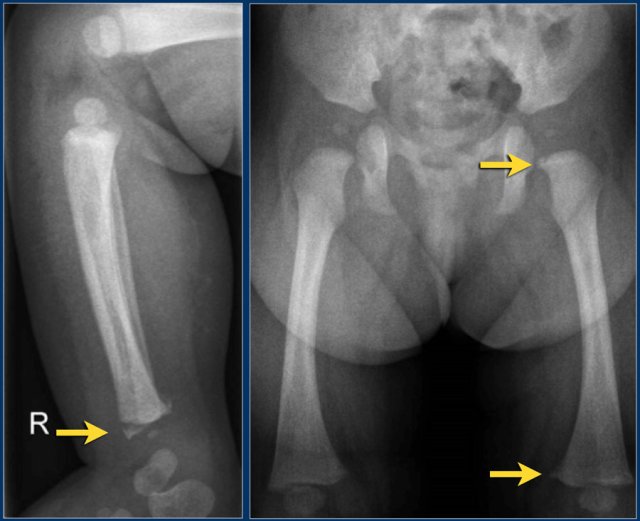

Slipped Capital Femoral Epiphysis (SCFE) or femoral epiphysiolysis is an idiopathic Salter-Harris type I fracture of the proximal femoral epiphysis.

It occurs more commonly in boys and in obese children. The typical age at presentation is between 12-15 years.

SCFE may occur bilaterally in up to one third of cases.

The epiphysis slips posteriorly, and to a lesser extent medially.

It is therefore best appreciated on the frog-leg lateral view.

SCFE is treated with surgical fixation to prevent further slippage.

Avascular necrosis of the femoral epiphysis is a potential complication.